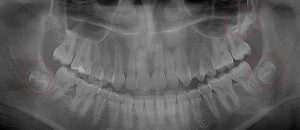

This 19 year old patient has all four 3rd molars present (circled). Only the upper left 3rd molar has fully erupted. The lower left 3rd molar is partially exposed and decaying while the lower right soft tissue impacted, both requiring extraction. Note the double crown on the upper right third molar.